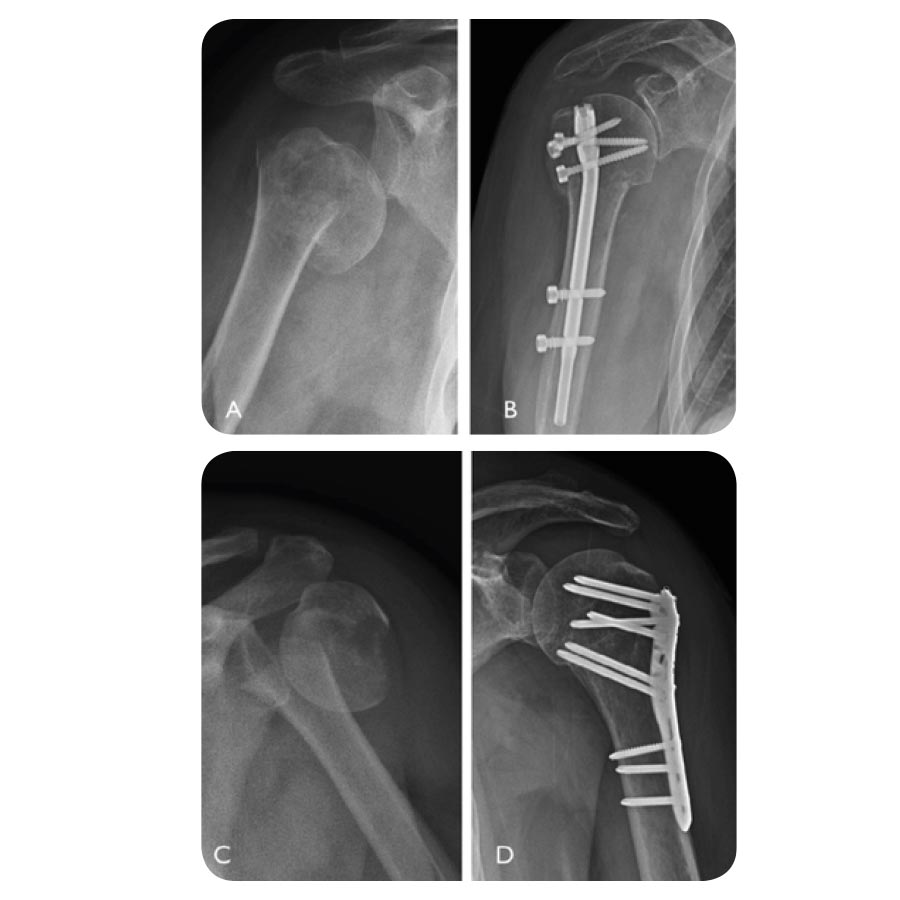

Les fractures de l’extrémité supérieure de l’humérus sont fréquentes. Il en existe différents types. Elles peuvent donner lieu à une immobilisation plus ou moins longue, parfois après une intervention chirurgicale.

Dans tous les cas, la rééducation devra être mise en œuvre afin de récupérer une fonction optimale. Cette rééducation sera longue et nécessitera une participation importante de votre part afin de minimiser le risque de séquelles. Après le traumatisme, une radiographie est réalisée. Elle est analysée par le médecin qui évalue en fonction de votre âge, de vos activités, du type de fracture et d’autres facteurs médicaux, le traitement qui permettra la meilleure récupération. Parfois un scanner peut être nécessaire avant de décider de procéder à une intervention chirurgicale. 80% des fractures de l’épaule ne nécessitent pas de chirurgie.